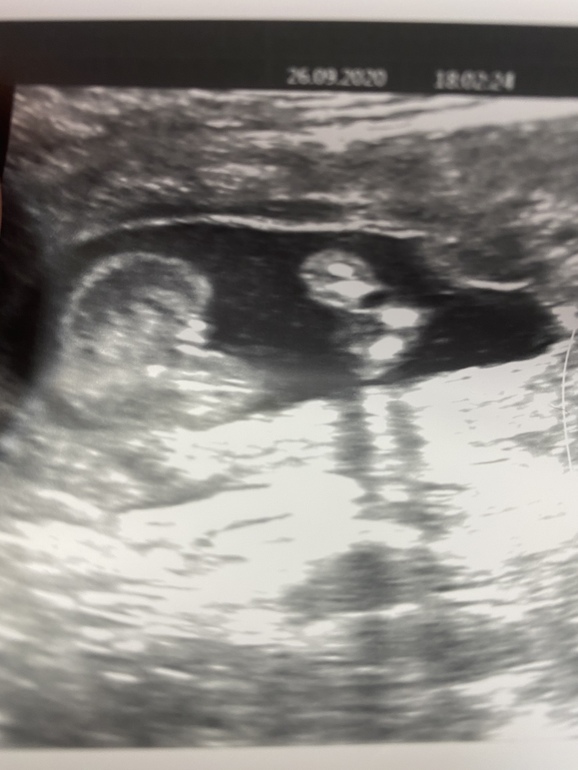

УЗИ, КТГ, доплерВсем привет ходили сегодня на скрининг платный всё слава богу хорошо весим 208 гр лежит поперёк не сильное предлежание плаценты сказал подняться должна.А самое главное у нас девочка🥰🥰🥰посмотрите это же точно?Мамы девочек у вас такие же пирожки?

Я пока разобрала, где попец, а где девчачьи прелести, телефон по часовой и против часовой стрелки несколько раз перевернула)). Она, не сомневаетесь